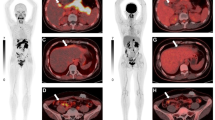

A case example of a 54-year-old female, with a previous history of treated localised breast cancer, and previously resected grade 1 (Ki-67 2%) pancreatic NET. She presented with new, multiple hepatic (A) and mesenteric nodal metastases (B). A Ga-68 DOTATATE PET/CT (C) showed metastatic disease in the liver, nodes and bones with high SSTR expression. FDG PET/CT (D) showed some lesions with concordant FDG avidity. The lesion with the highest metabolic activity (mesenteric node, E) was targeted for biopsy and diagnosis. Histopathology (F) showed monotonous cuboidal cells with granular eosinophilic cytoplasm, ovoid nuclei and fine chromatin. By IHC Ki-67 labelling index was 25% (G) and DAXX expression was lost (H). Other IHC (not shown) demonstrated expression of SSTR2 and synaptophysin, retained ATRX and Rb, a p53 wild-type pattern, and no staining for chromogranin or multiple breast markers. Overall, the features were supportive of a G3 NET and not breast carcinoma or NEC. Genomic sequencing confirmed DAXX mutation and MEN1 mutation, typical for NET. The patient proceeded to receive PRRT treatment for metastatic G3 NET

Dr. Catherine Mitchell reported the histopathology displayed in Fig. 1.